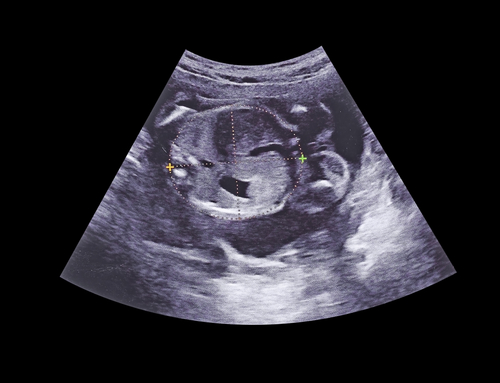

妊娠5ヶ月に入ると、赤ちゃんの体重は約100~250g程度まで増えています。赤ちゃんの大きさは約200mmまで大きくなり、エコー検査で見ても手足などがはっきりわかり、人の形であることを確認できます。赤ちゃんの頭の大きさは鶏の頭くらいで3頭身になっています。

妊娠5ヶ月には男の子も女の子も性器形成が発達し、運が良ければこのタイミングで性別が判断できる場合もあります。特に男の子の場合は、エコー検査でお股が見えていれば判別しやすいです。しかし、赤ちゃんが背中を向けていたり足を組んだりしている場合は見えづらいので、妊娠5ヶ月になったから必ず性別がわかるとは限りません。

つわりの有無に限らず、安定期に入ると体調がぐっと良くなったという妊婦さんは多いでしょう。エコーで見る赤ちゃんの様子もぐっと人間らしくなりますし、胎動を感じる人もいて、赤ちゃんがお腹にいるんだ、とより実感できる時期でしょう。